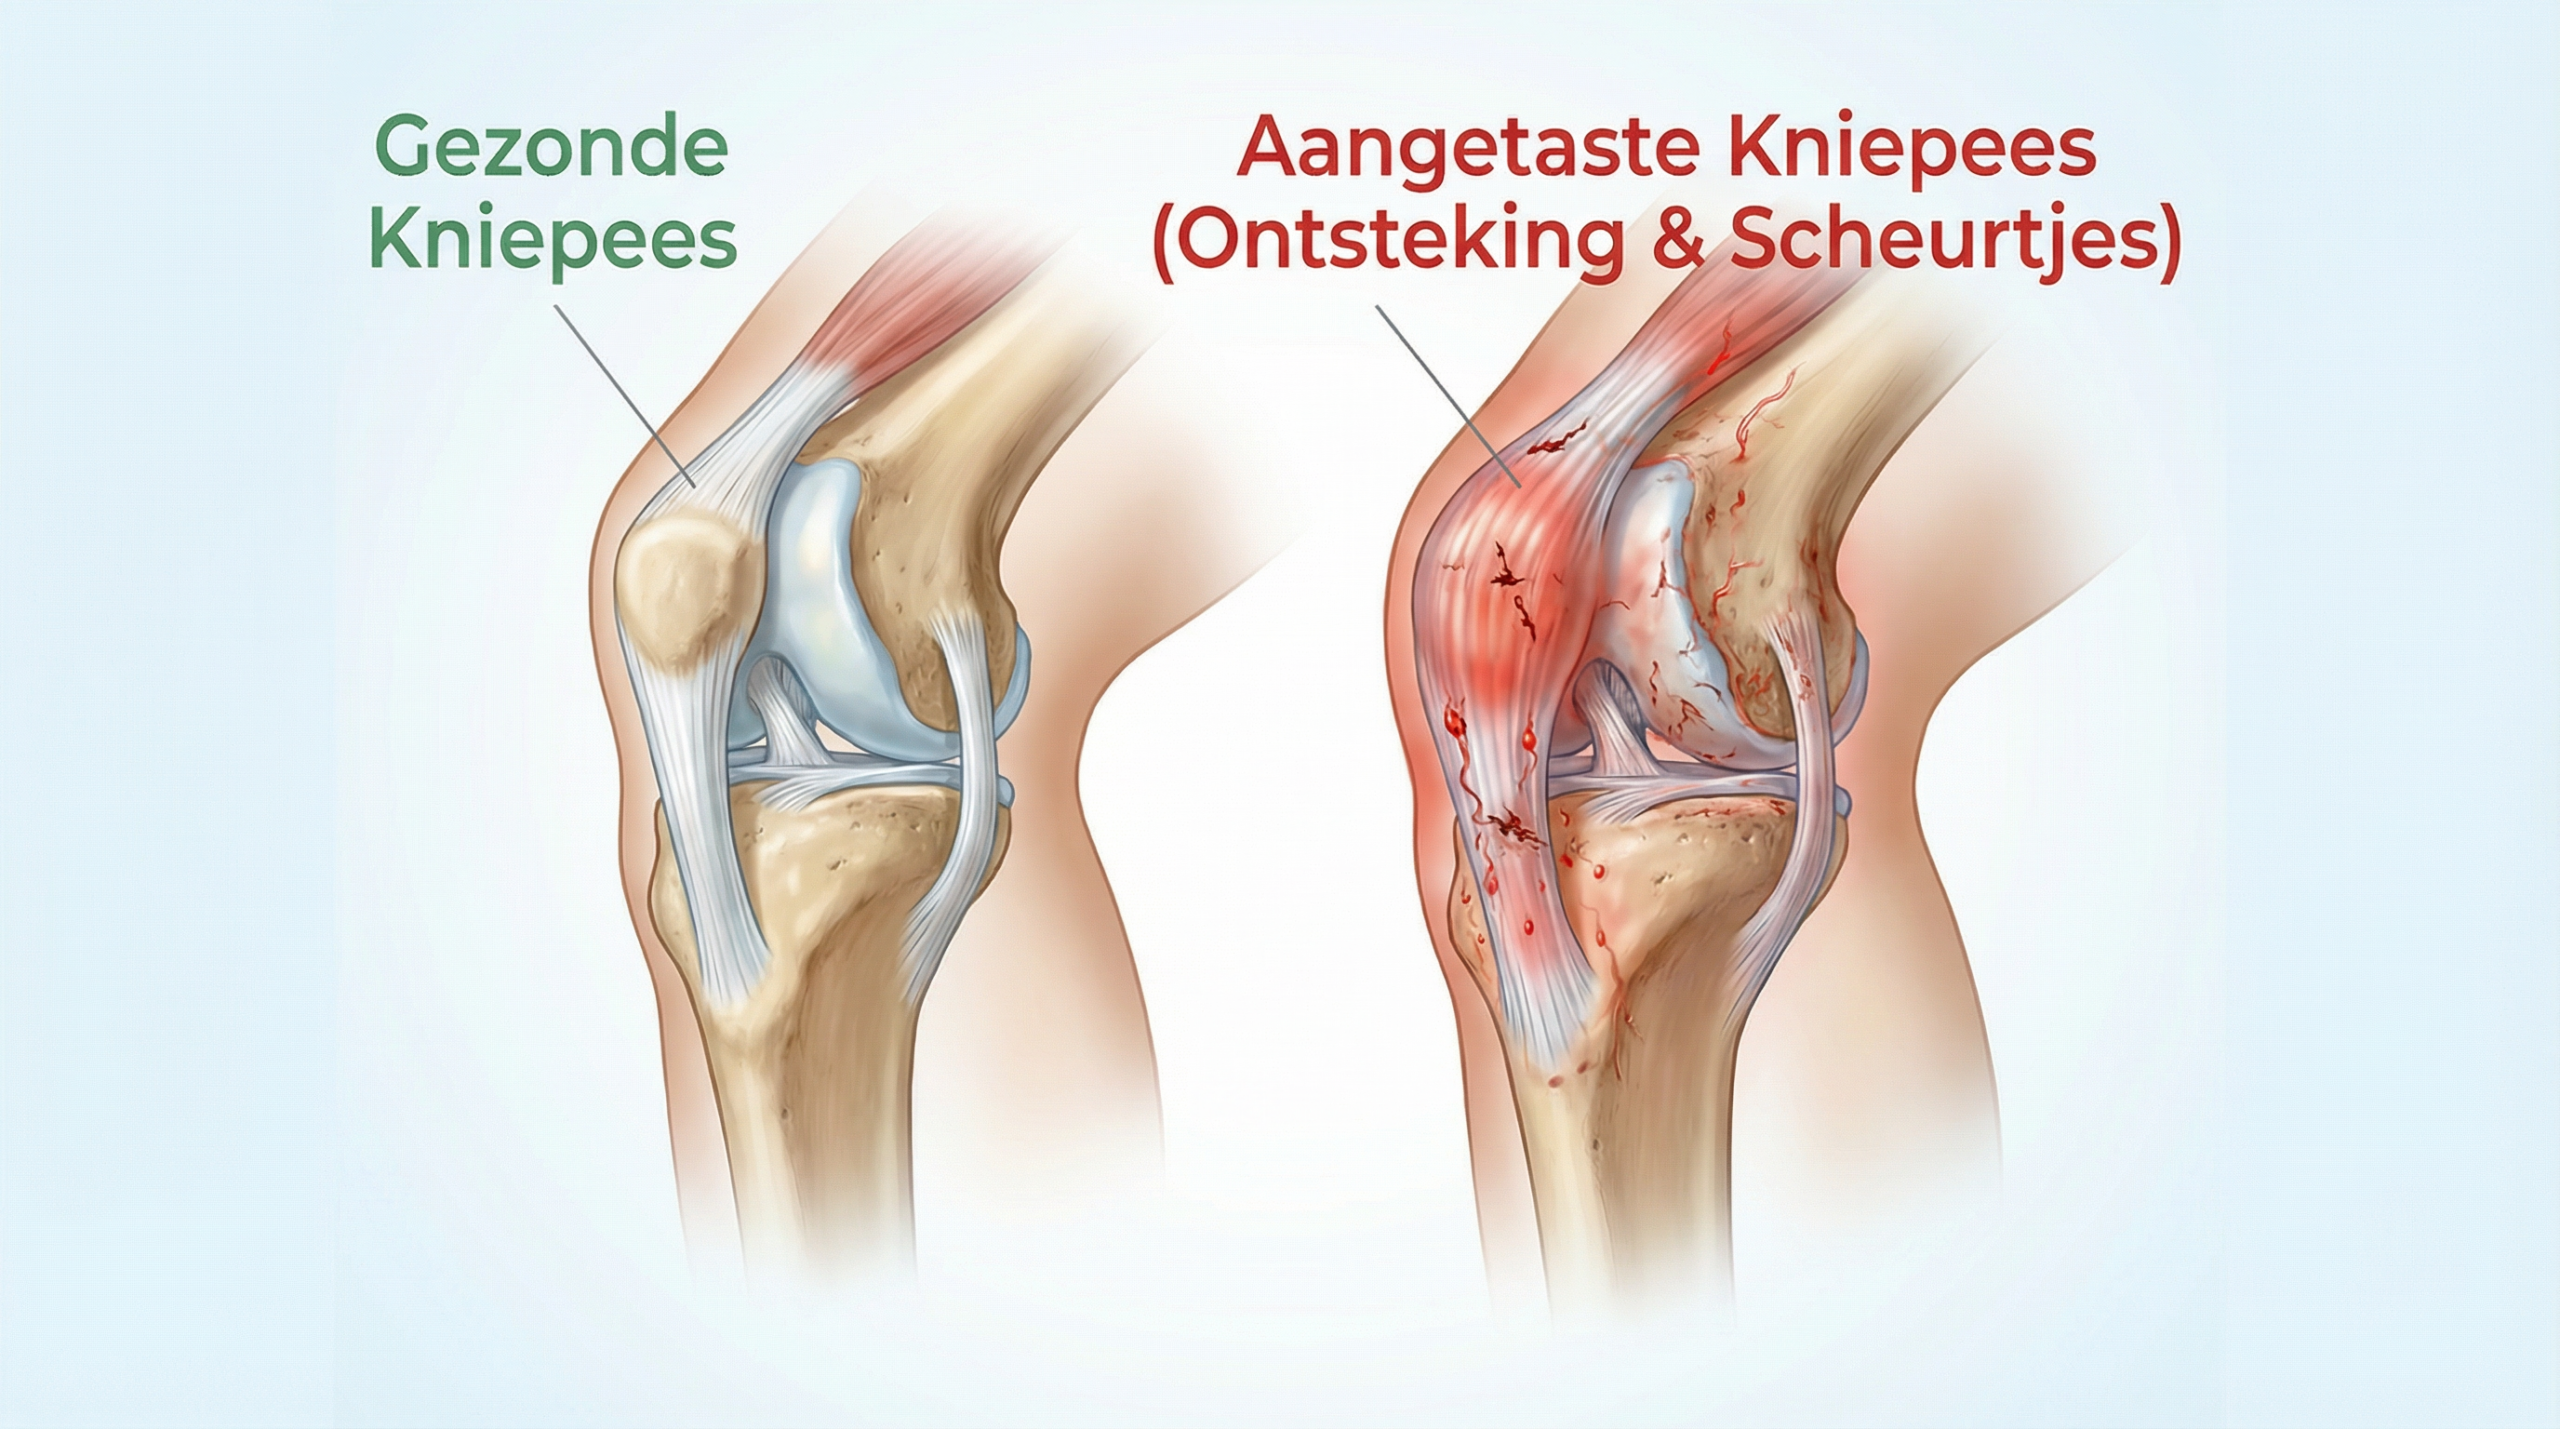

Kijk nu naar een aangetaste kniepees.

Het peesweefsel vertoont microscheurtjes en de collageenvezels zijn dunner en ongeordend geworden — doordat de ontstekingssignalen die normaal voor herstel zorgen, chronisch geactiveerd blijven en het weefsel van binnenuit aantasten.

Het is als een touwbrug met slijtende kabels die bij elke stap en sprong verder onder druk staan.

Als We De Ontsteking Aan De Knie Niet Aanpakken, Wordt Het Alleen Maar Erger

Wanneer dit gebeurt, blijft de ontsteking in de kniepees actief en neemt de structurele beschadiging toe — wat leidt tot steeds meer pijn bij elke kniebeweging.

En net als bij die slijtende kabels van de touwbrug…

De kniepees heeft geen bescherming meer…

De pees raakt steeds verder beschadigd van binnenuit…

En zo beginnen de pijn, de stijfheid en de beperkingen toe te nemen.